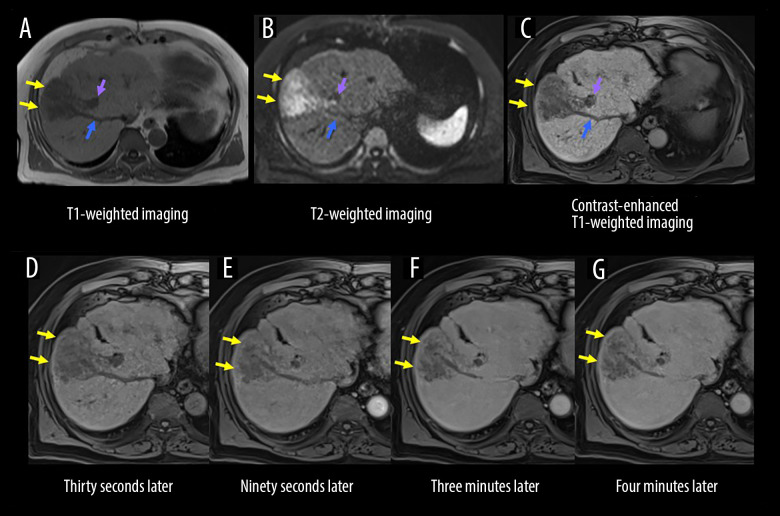

原发性肝神经内分泌肿瘤(PHNENs),包括原发性肝神经内分泌癌(PHNEC),是非常罕见的。尽管混合神经内分泌-非神经内分泌肿瘤预后较差,但PHNENs通常表现为生长缓慢。PHNENs的诊断也具有挑战性。病例报告一名73岁男性接受CT平扫时,偶然发现一个42毫米的孤立性肝脏肿瘤。缺乏维生素K或PIVKA-II诱导的血清蛋白水平升高至138 mAU/mL。13天后,磁共振成像(MRI)显示肝脏肿瘤扩大,肿瘤血栓延伸到肝静脉和门静脉。未观察到早期增强。第18天,多普勒超声和动态CT评估肿瘤为低血管,并出现新的肿胀的孤立淋巴结。第39天,正电子发射断层扫描(PET)/CT显示原发性肝脏肿瘤和转移性淋巴结强烈摄取,并出现其他远处淋巴结转移。第49天,手术切除转移性颈部淋巴结。在第61天,根据组织病理学和免疫组织化学评估明确诊断PHNEC。Ki-67标记指数为90%。在第67天,他住院开始化疗,但CT显示终末期疾病。需要姑息治疗,患者在最初诊断后82天死于癌症。结论:我们报告了一个令人深思的PHNEC病例,肿瘤进展迅速。为了阐明临床意义(例如,非典型影像特征和诊断缺陷),提供了详细的影像结果。我们期望这个病例将对该领域的临床医生提供信息。

BACKGROUND Primary hepatic neuroendocrine neoplasms (PHNENs), including primary hepatic neuroendocrine carcinoma (PHNEC), are extremely rare. PHNENs typically exhibit slow growth, although mixed neuroendocrine-non-neuroendocrine neoplasms have poor prognoses. PHNENs are also challenging to diagnose. CASE REPORT A 73-year-old man underwent plain computed tomography (CT), which incidentally detected a 42-mm solitary hepatic tumor. Serum levels of protein induced by vitamin K absence or antagonist-II (PIVKA-II) were elevated at 138 mAU/mL. Thirteen days later, magnetic resonance imaging (MRI) revealed an enlarged hepatic tumor with tumor thromboses extending into the hepatic and portal veins. No early-phase enhancement was observed. At 18 days, Doppler ultrasound and dynamic CT evaluated the tumor as hypovascular, and a newly swollen solitary lymph node appeared. At 39 days, positron emission tomography (PET)/CT revealed strong uptake in the primary liver tumor and metastatic lymph nodes, with additional distant lymph node metastases emerging. At 49 days, a metastatic cervical lymph node was surgically resected. At 61 days, PHNEC was definitively diagnosed based on histopathological and immunohistochemical assessments. The Ki-67 labeling index was >90%. At 67 days, he was hospitalized to begin chemotherapy, but CT revealed end-stage disease. Palliative treatment was required, and the patient died of cancer 82 days after the initial diagnosis. CONCLUSIONS We have presented a thought-provoking case of PHNEC with rapid oncological progression. To clarify clinical implications (eg, atypical imaging features and diagnostic pitfalls), detailed imaging findings are provided. We anticipate that this case will be informative for clinicians in this field.